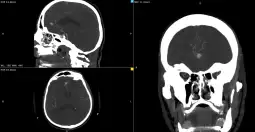

Скопје, 19 септември 2025 (МИА) - На Универзитетска клиника за неврохирургија е извршена комплексна микрохируршка интервенција кај 57-годишен пациент со руптурирана аневризма на мозочен крвен сад.

- Станува збор за операција која за првпат во Македонија е изведена со примена на интраоперативна флуоресцентна видеоангиографија. Оваа иновација е значаен чекор напред во модернизацијата на македонското здравство. Примената на интраоперативната флуоресцентна видеоангиографија ја зголемува безбедноста на пациентите и ја подобрува ефикасноста на хируршките интервенции, вели министерот за здравство Азир Алиу.

Оваа иновативна метода претставува напредна техника која овозможува визуелизација на крвниот проток во реално време за време на операцијата.

- Со примена на контрастно средство, хирурзите можат прецизно да ја проценат проодноста на крвните садови и да го потврдат целосното исклучување на аневризмата, што е клучно за успешен исход, појаснува д-р Благој Шунтов, специјалист по неврохирургија и раководител на тимот.

Операцијата помина без компликации, а пациентот се опоравува без потешкотии. Примената на оваа напредна техника претставува значаен напредок во третманот на неврохируршки пациенти и ја потврдува посветеноста на Клиниката за неврохирургија во примена на најновите медицински технологии. Оваа иновација претставува значаен чекор напред во модернизацијата на македонското здравство и ја потврдува посветеноста на здравствените институции во примената на најновите медицински технологии, информираат од Министерството за здравство. рп/са/

Фото: МЗ